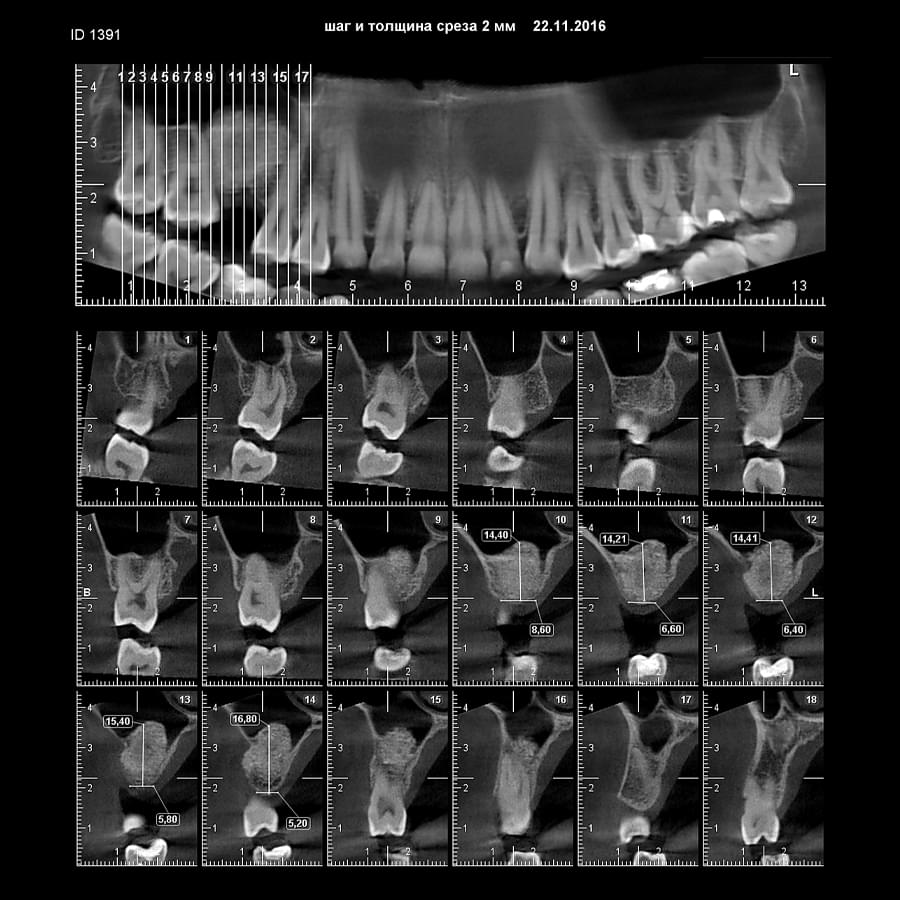

Ми розуміємо, наскільки важлива деталізація в ендодонтії та терапевтичному лікуванні.

Завдяки флагманському обладнанню PLANMECA, ми отримуємо знімки з мінімальним рівнем шумів та

високою роздільною здатністю, що дозволяє чітко візуалізувати морфологію кореневих каналів,

приховані каріозні порожнини та стан періапікальних тканин.

Крім того, ми маємо власний сервер, на

якому створюємо окрему скриньку для кожного лікаря, що забезпечує максимальну зручність та

ефективність роботи.